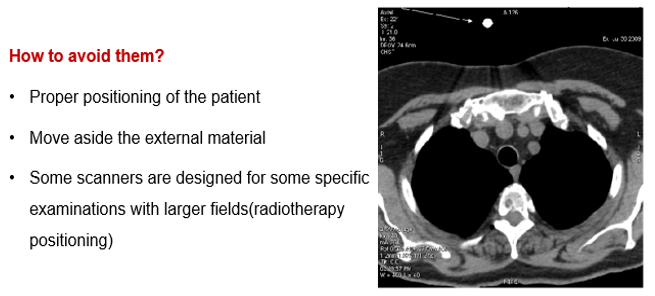

Exterior Elements

Exterior materials such as ECG leads, O2 tubes or limbs can cause artifacts. The technologist should put the patient in the correct position and then move them out of the way possible.

For example, arms along the side of the patient’s body can cause an undesirable artifact. Notice the streaking in this image.